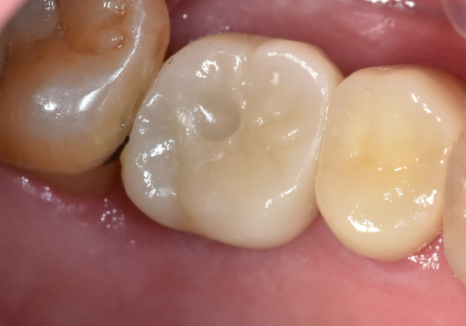

240812

충치가 있긴 했지만

치아 뿌리는 튼튼했기에,

치아 내부의 오염된 신경관을

청소하는 신경치료를 진행했습니다.

251010

오염된 신경을 4번에 걸쳐

꼼꼼히 제거하고 소독한 뒤,

이번에는 구멍이 잘 나지 않는

단단한 재료인 '지르코니아'로 씌워,

튼튼하게 마무리해 드렸습니다.

251103